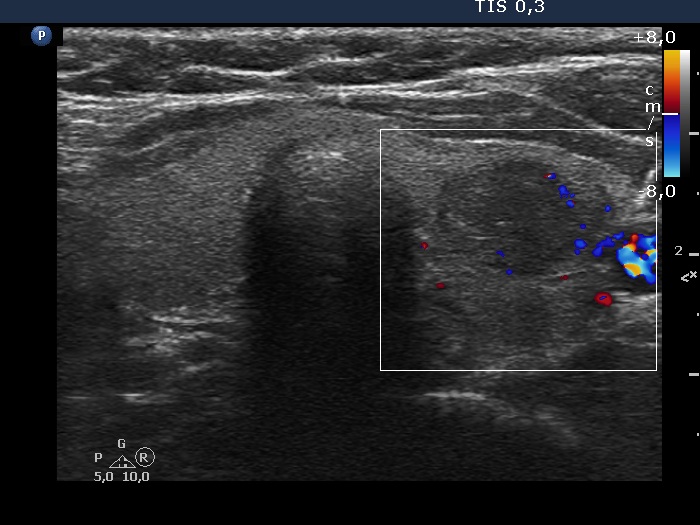

The echogenicity of the nodule - case 2064 (ultrasonographic picture 3)

Left lobe, transverse scan, color Doppler mode. The vascularization is not specific.